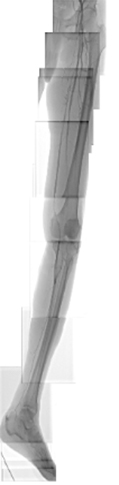

当院では、最新式の下肢静脈瘤に対するレーザー治療機器ELVeSレーザー1470を使用しています。高周波治療でも治療効果はこの機器と同等と言われています。基本的には下肢静脈超音波検査、下肢単純CT撮影で手術適応、手術術式を決定しています。必要な場合には適宜検査を追加いたします。